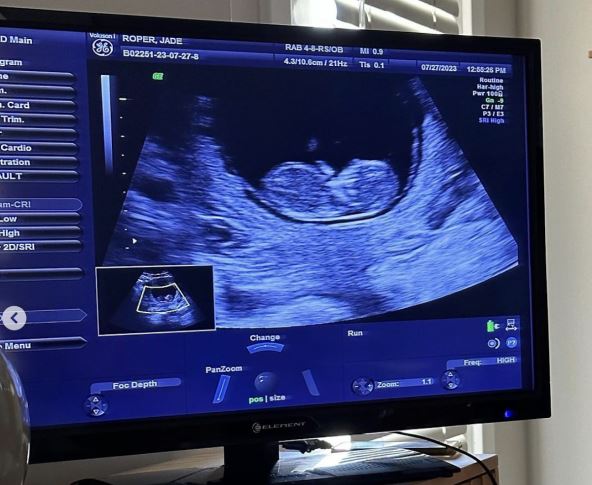

"Mučila sam se šta da vam napišem, jer trenutno prolazim kroz takozvani propušteni pobačaj. Srce mog sina prestalo je da kuca, i prestao je da raste pre nekog vremena. Ali moje telo još uvek nije okončalo trudnoću. Nadam se da će se to dogoditi prirodno", napisala je ona uz sliku na kojoj nežno drži svoj trudnički stomak, i još slika sa ultrazvuka.

ultrazvuk

Foto: Instagram/jadelizroper